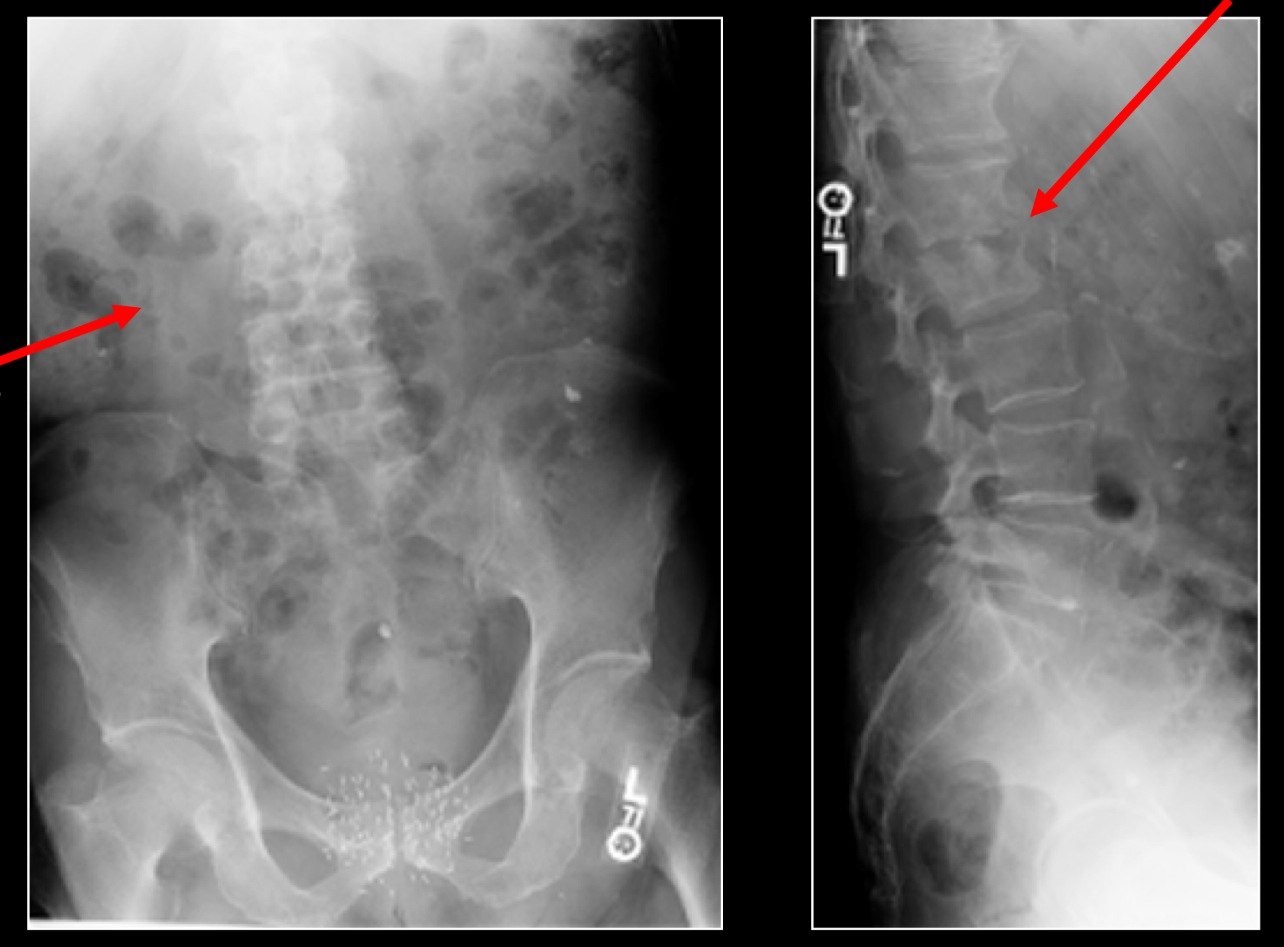

Дифференциальная диагностика болезни Потта включает обзорную рентгенографию и томографию пораженного участка позвоночника в двух проекциях.

Для определения источника инфекции применяются стереофистулография и абсцессография. Оценка уровня и степени распространения патологии спинного мозга осуществляется с помощью пневмомиелографии, при которой контрастом служит кислород, вводимый во время люмбальной пункции.

Также необходимо провести веноспондилографию позвоночника, что позволяет точно оценить степень сосудистых нарушений при туберкулезном спондилите. Эффективность диагностики во многом зависит от качества рентгеновских снимков.

Для выявления заболевания часто используют компьютерную томографию и боковые рентгенограммы грудной клетки (переднезадние). Современно оборудованные медицинские центры предлагают анализ титров тифоидных и паратифоидных инфекций для диагностики болезни Потта. В сложных случаях может потребоваться игловая биопсия.